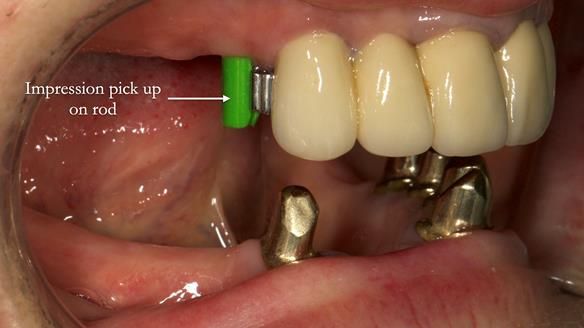

Replacement lower overdenture & upper RPD for Jackie

This Newsletter show Jackie’s case from start to finish – a technically demanding case involving replacing a telescopic crown-supported lower overdenture and an upper precision attachment-retained partial denture.